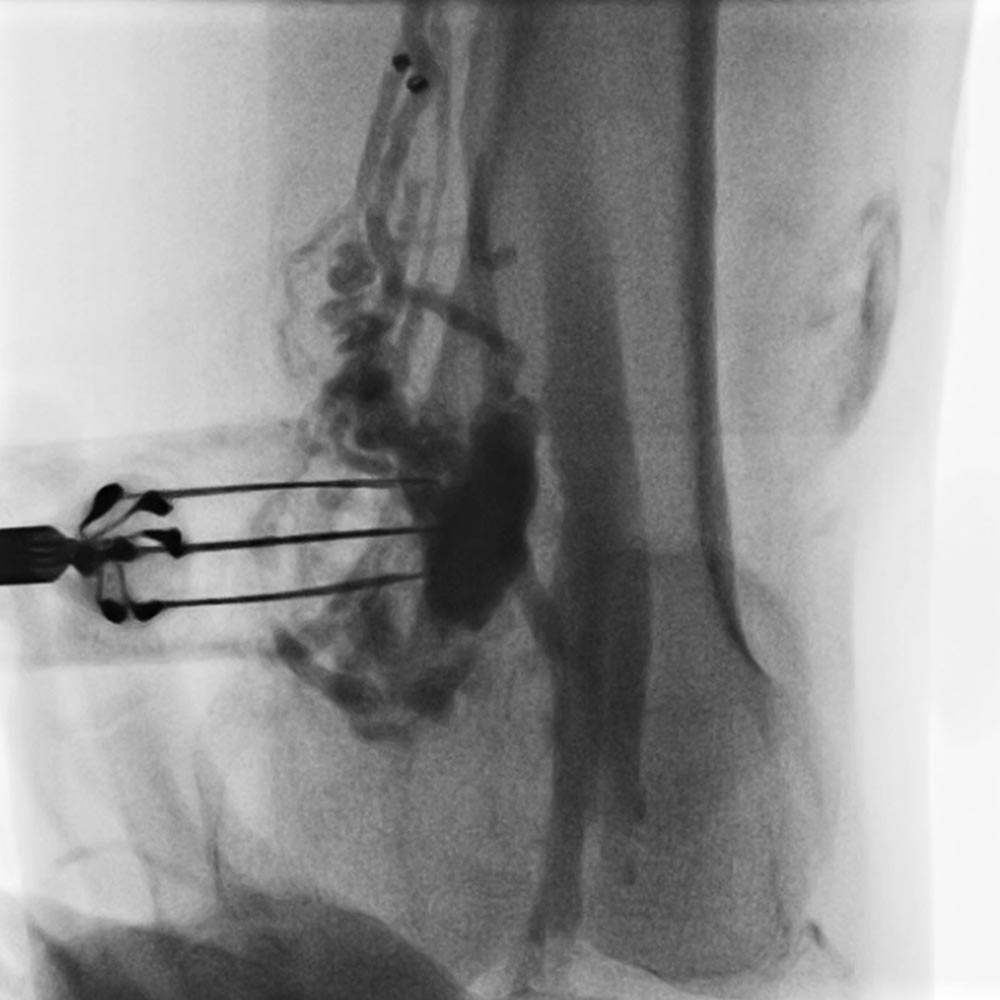

For the subsequent reversible electroporation, there is a variety of different needle geometries and applicators available to suit the particular patient. Electrodes can be selected according to the size, type, location, extent and accessibility of the individual lesion. The thin needles are then inserted into the target lesion under ultrasound guidance, sometimes also under fluoroscopy, and connected to the pulse generator. The exact needle geometry of the specific applicator then determines not only  conductivity measurements in the lesion but also the final impulse protocol to be employed. The applied pulses are adapted to the specific malformation in the individual patient and its tissue characteristics.